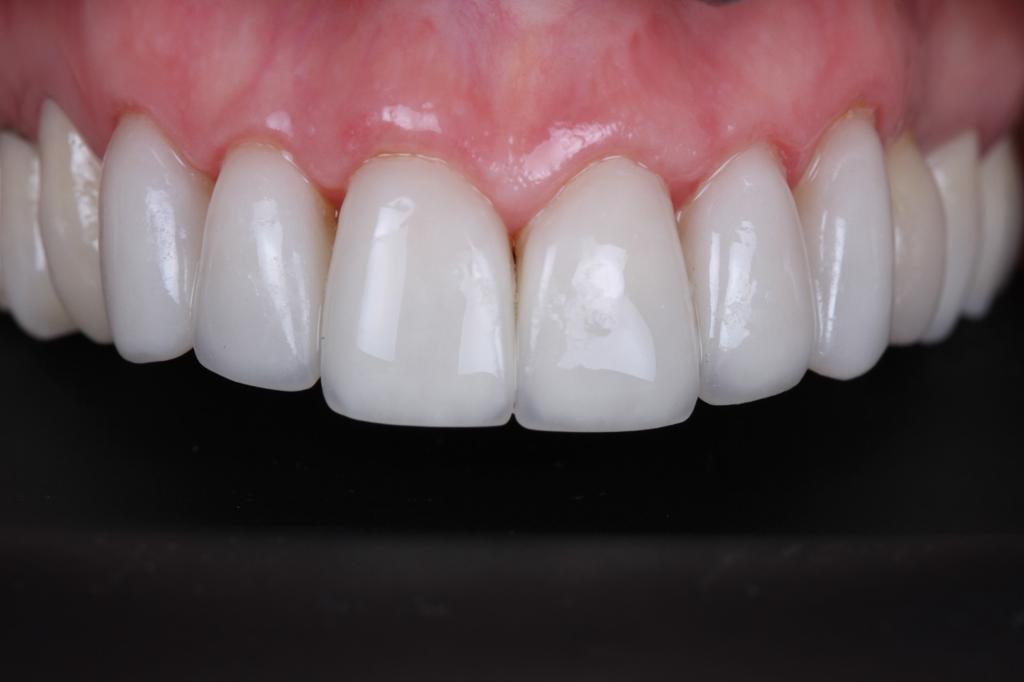

Виниры полевошпат

Пациентка обратилась в клинику на профилактический осмотр , было выявлено, что под ранее установленными винирами есть кариозные поражения. Наш доктор Кациев М.М. принял решение заменить виниры с 13 по 23 зубы.

Предварительно, перед установкой новых виниров , было проведено лечение по кариесу. Пациентка осталась довольна.